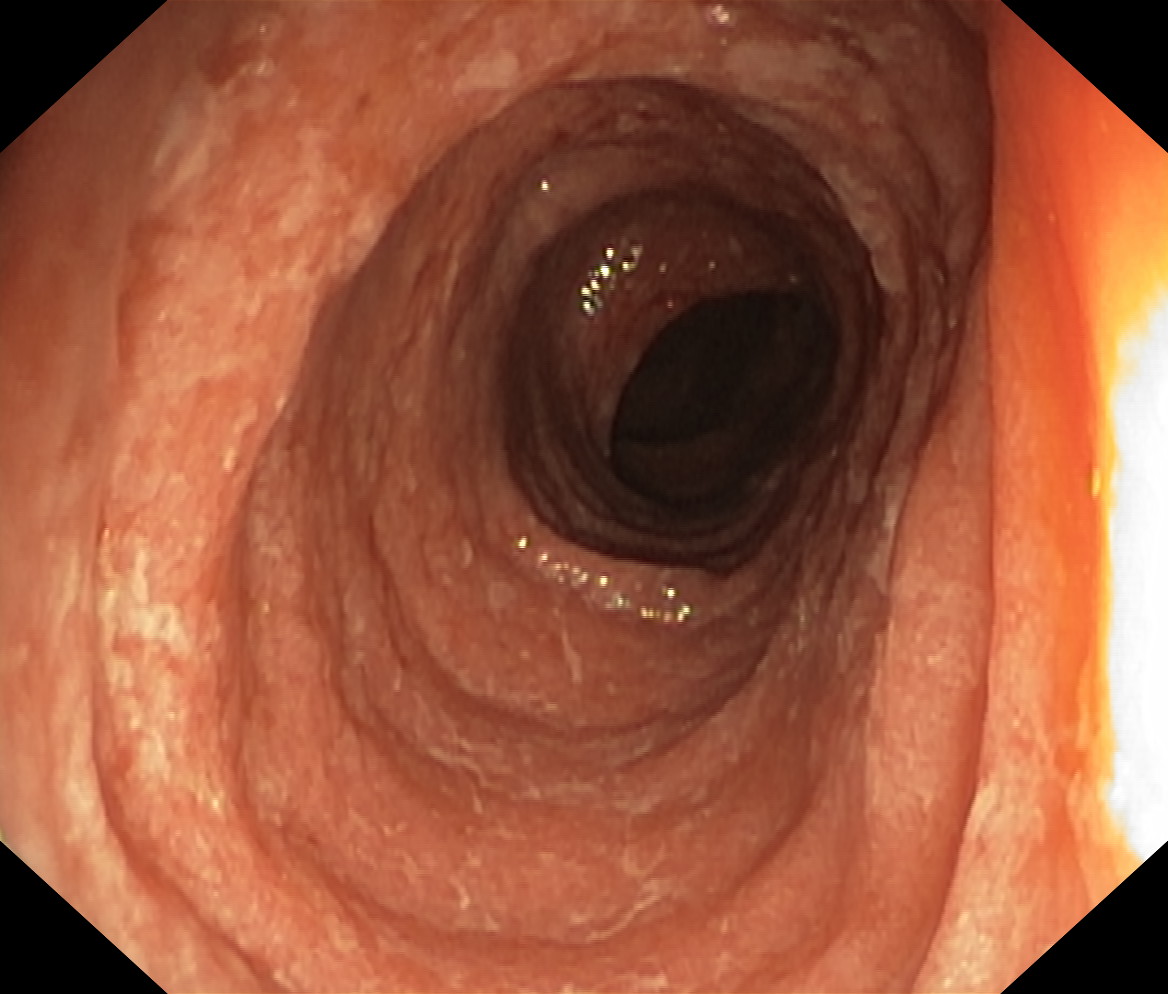

Zapalenie wrzodziejące jelita grubego